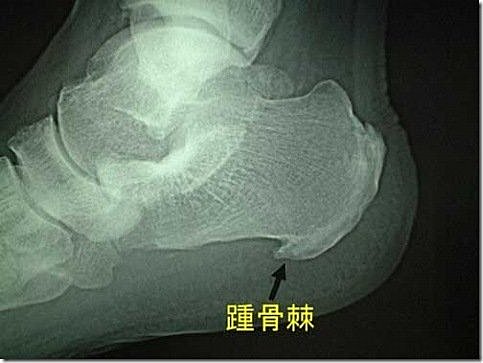

骨刺是脊椎退化過程中所伴隨的一種現象,隨著年齡的增長,人體的脊椎構造也會跟著退化,當骨頭與軟組織接壤的地方因長期承受壓力、拉力、損傷,造成脊椎與脊椎間的軟骨漸漸失去水分與彈性,致使骨骼出現退化性改變,這種骨骼退化性改變就會導致骨質增生,而形成骨刺。另外,反覆活動或不適當的運動,也常會使關節部位的骨骼及軟組織過度磨損,而長出骨刺。骨刺一般好發於活動較頻仍的關節,由於這些關節長時間反覆使用,因此很容易發生磨損與退化的現象。而身體容易誘發骨刺生長的地方包括頸椎、腰椎、膝關節、腳跟,另外,手指跟手肘也是骨刺容易發生的部位。

其實骨刺不見得一定會產生症狀,要看是否有壓迫到神經根或是脊椎,如果沒有的話就不會有什麼讓人不適的症狀產生。相反的,如果骨刺剛好壓迫到附近的神經根或是壓迫到脊椎,就可能會有身體僵硬不能靈活彎身、疼痛、紅腫、麻痺、關節變形、肌肉無力等症狀。發生骨刺可能出現的三種情況:第一種是沒有任何症狀。許多人是因為有其他病症,在接受X光檢查時才發現「骨刺」;這種現象顯示,關節軟骨已發生某種程度的損傷,而身體已作了相當的修補。第二種情況是,局部關節會感到疼痛,出現發炎的症狀或功能異常。這往往是關節炎本身變化所引起,而不完全是骨刺之過。第三種則是骨刺引起了併發症,例如在它附近的軟組織,尤其是神經,受到刺激或壓迫時,會使病人疼痛難當。併發症的程度及嚴重性,完全因受壓迫的部位而異。